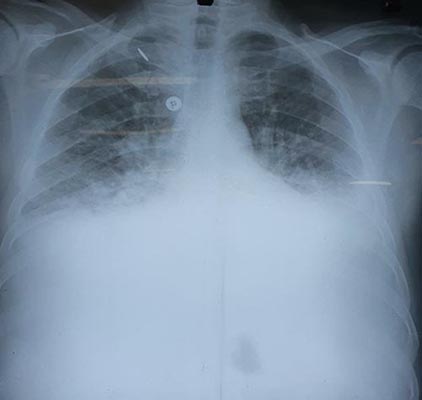

Paciente realizou um rx torax na admissão: